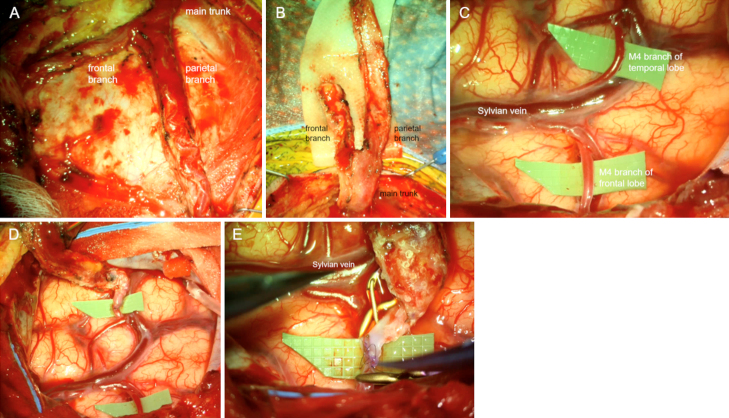

Observations: A 38-year-old male with OI type I presented with a symptomatic left internal carotid artery (ICA) occlusive dissection managed with endovascular revascularization and stenting. Follow-up surveillance imaging identified an incidental right ICA dissection, also treated with stenting. Four years later, the patient experienced new right hemispheric symptoms. He was found to have progressive right ICA dissection on best medical management. Following an unsuccessful restenting attempt, he underwent a successful double-barrel superficial temporal artery-to-middle cerebral artery (STA-MCA) bypass to restore cerebral perfusion with no perioperative complications. Six-month follow-up DSA confirmed a patent bypass with robust flow, and the patient remained asymptomatic 1 year postoperatively.